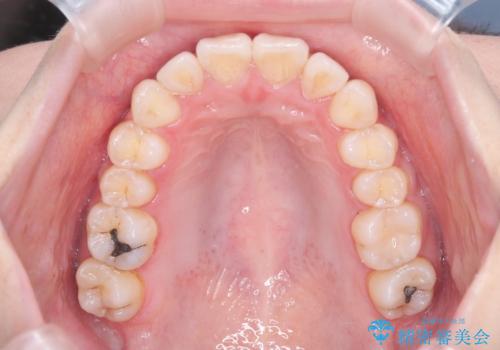

反対咬合を治したい。インビザライン

- 前歯の反対咬合を治したいことを主訴に来院されました。

インビザラインにて臼歯の遠心移動を行いながら、スペースを作り反対咬合を改善することができました。